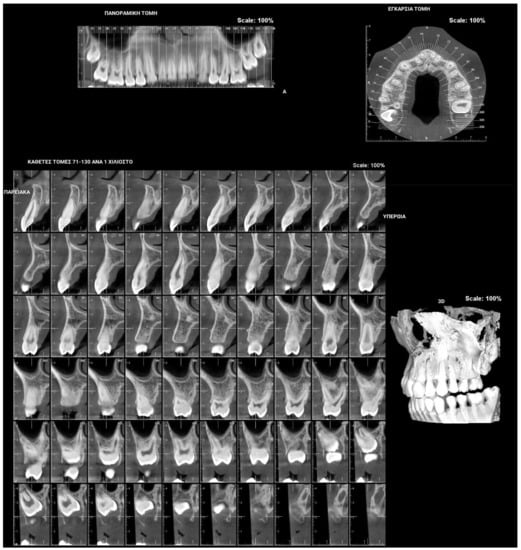

Figure 4.

Patient’s orthopantomography presenting Primary Failure of Eruption in all four dental quadrants.

PFE attributes combine elements that resemble both primary and secondary retention (Figure 4). The diagnosis of PFE is impeded to a great extent by the complexity of this clinical picture (Figure 5 and Figure 6). It appears that this clinical condition has two different mechanisms or two different aspects of the same mechanism since the tooth may erupt in its initial position and thereafter stop its further eruption (a clinical condition known as secondary retention) [7,8,14], or the tooth may not be able to erupt at all [11]. In this context, a definitive diagnosis of PFE cannot easily be decided, as it is possible that PFE presents two separate mechanisms [11] or two independent manifestations of the same mechanism. Only if we were to examine an environment where genetic, pathological, and environmental factors—all factors potentially responsible for the discontinuation of the tooth’s eruption—are absent would a PFE diagnosis through a retrospective examination be possible.

Figure 5 and Figure 6 present a PFE case of a 17-year-old female patient referred to the Orthodontic Clinic of the Dental School of the National and Kapodistrian University of Athens, Greece. Clinical examination showed a posterior open bite on the right segment, as well as infraoccluded left upper and lower first molars. The patient’s orthopantomography shows no visible PDL of the right upper and lower first molars or the teeth distally related to them.